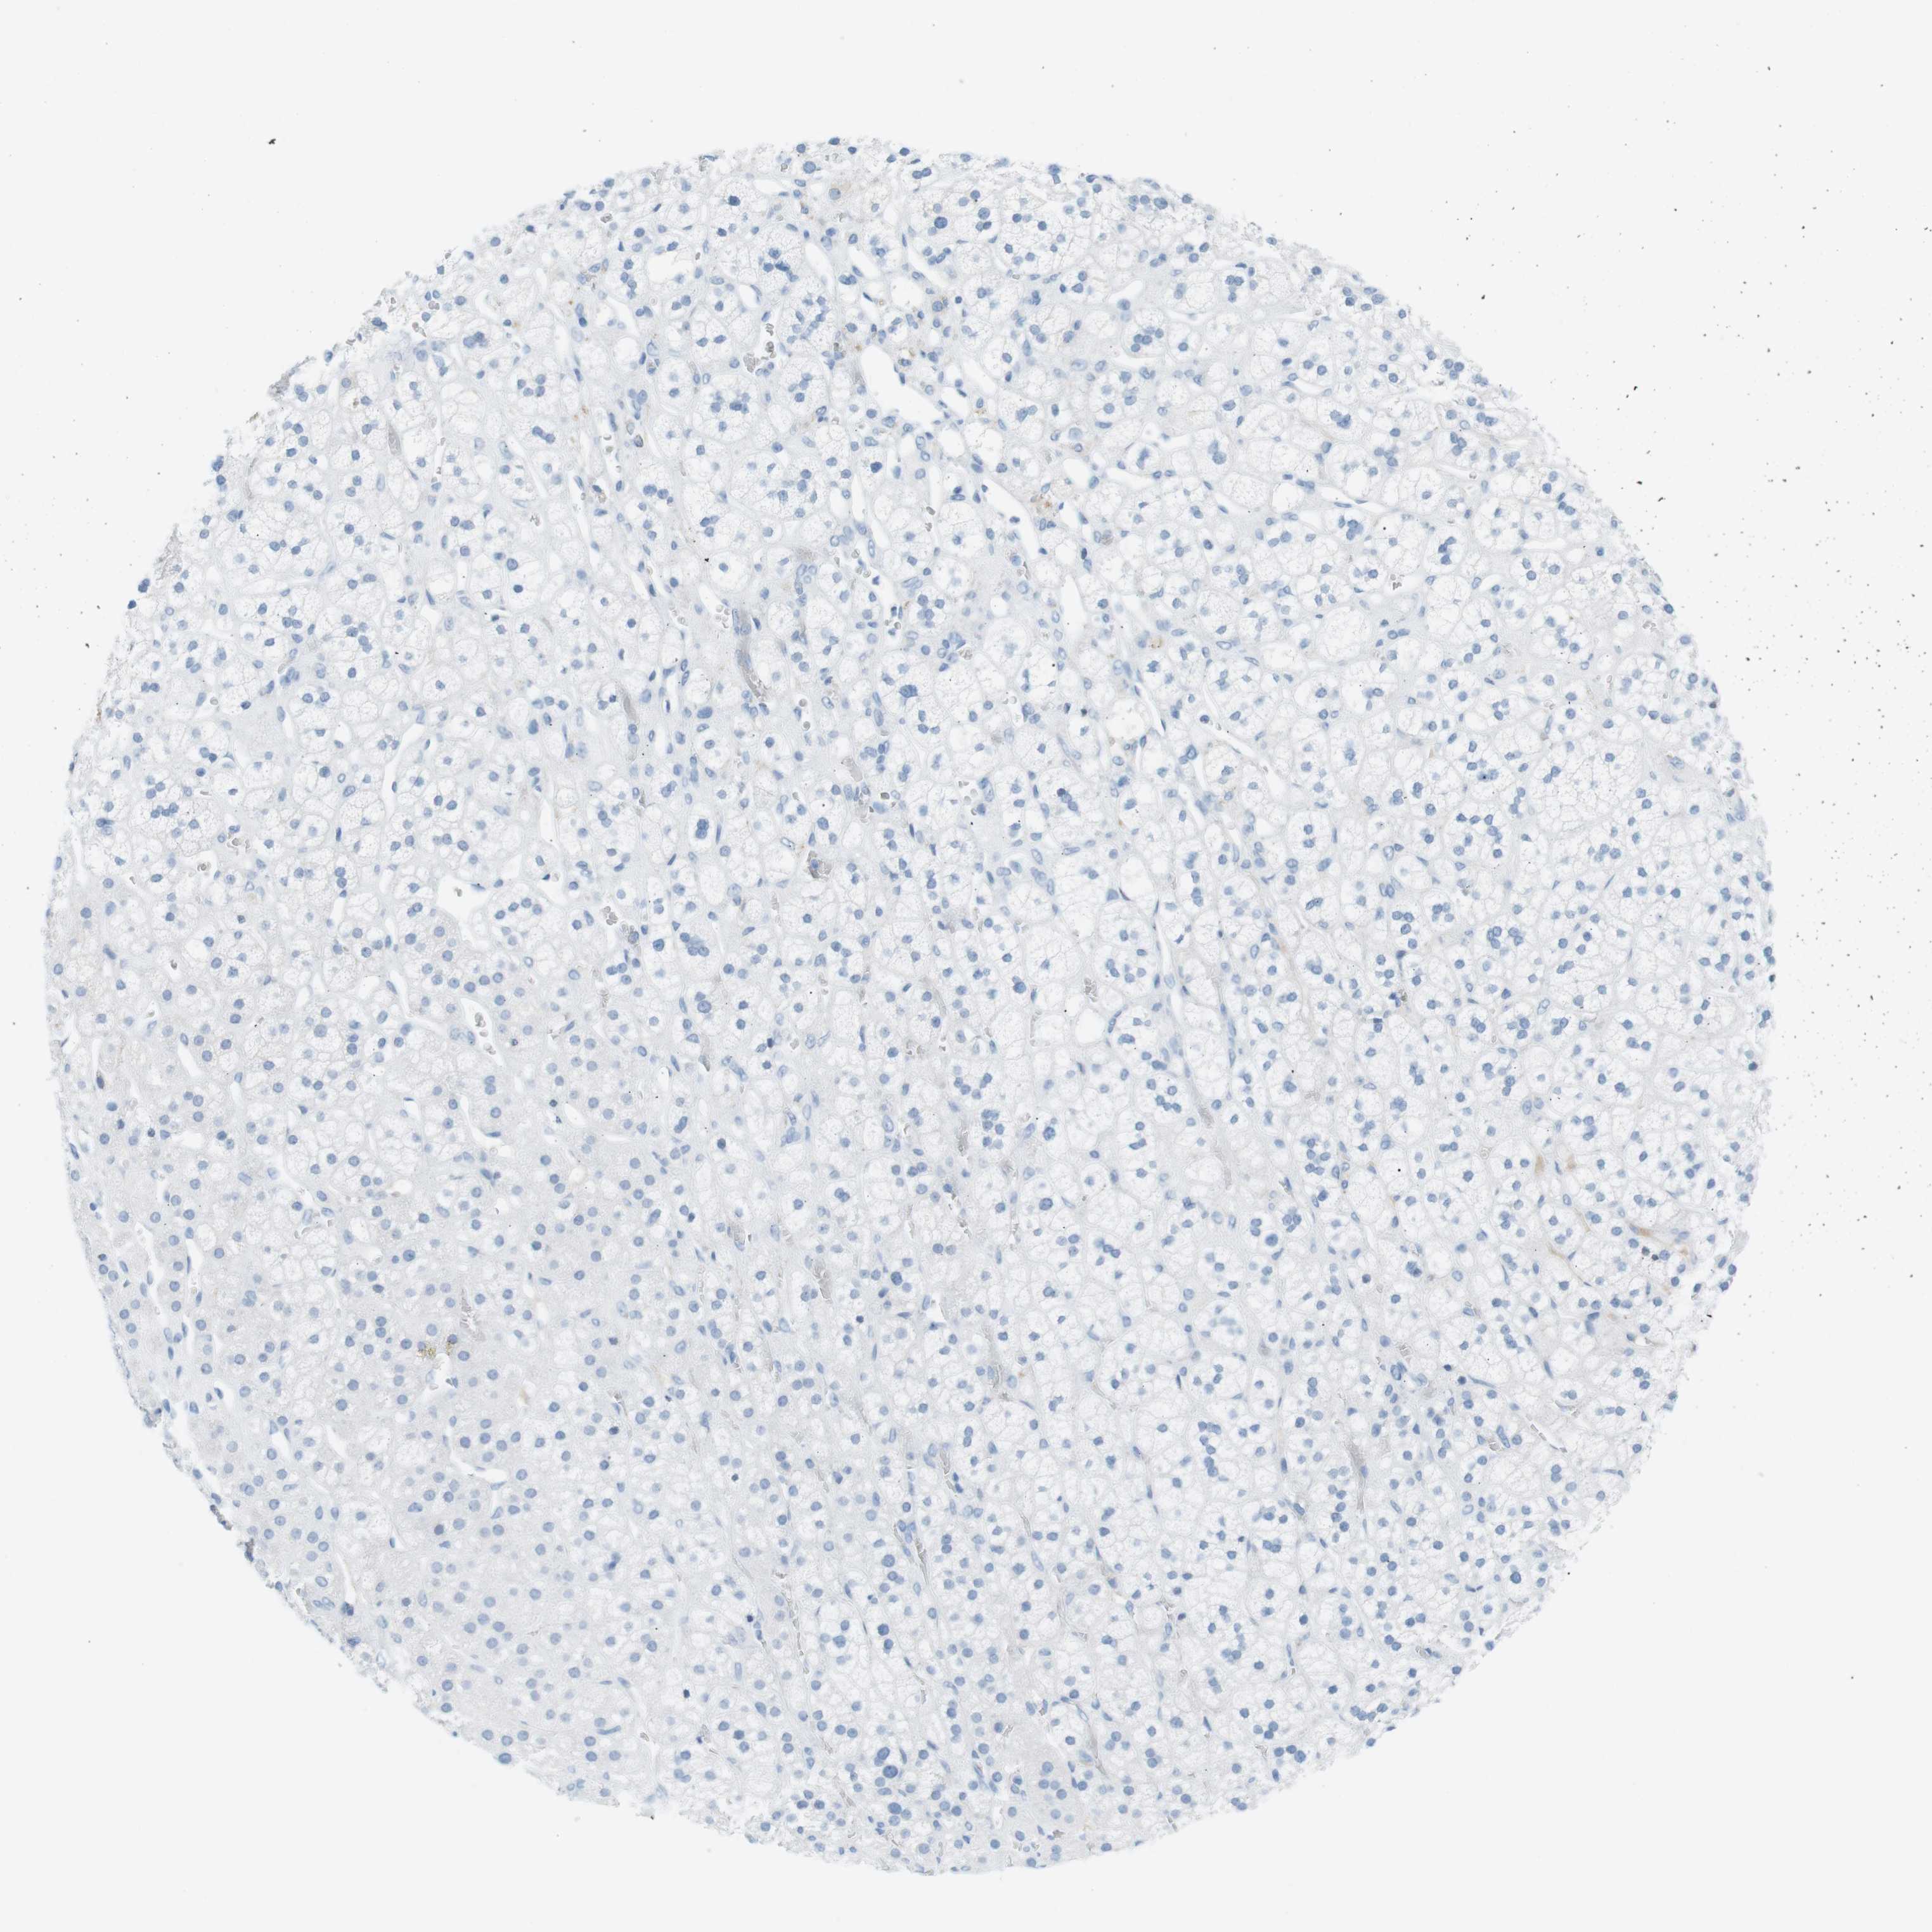

ADRENAL GLAND - Antibody stainingi

Antibody staining in the annotated cell types in the current human tissue is reported as not detected, low, medium, or high, based on conventional immunohistochemistry profiling in selected tissues. This score is based on the combination of the staining intensity and fraction of stained cells.

Each image is clickable and will lead to virtual microscopy that enables deeper exploration of all samples and also displays staining intensity scores, fraction scores and subcellular localization as well as patient and tissue information for each sample.

Antibody HPA012582Antibody CAB016087Antibody CAB032276

Glandular cells Not detectedNot detectedNot detected